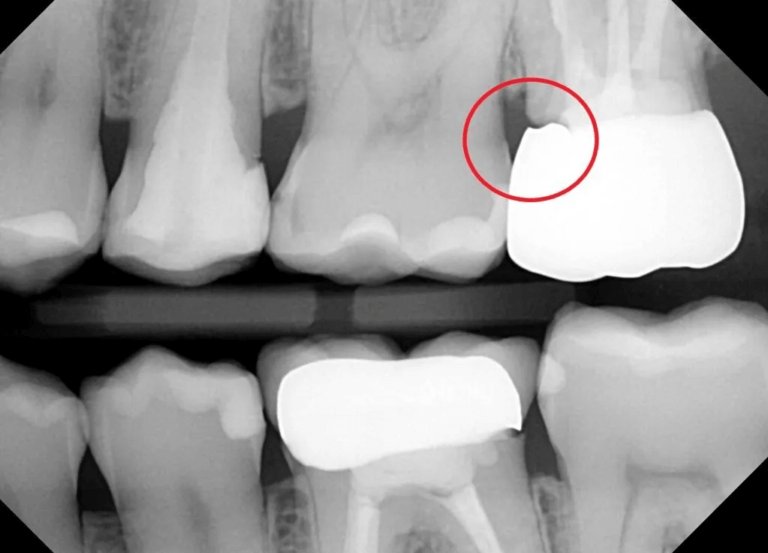

크라운의 엑스레이 사진입니다. 엑스레이 사진에서 크라운은 다른부분보다 하얗게 보입니다. 빨간색 동그라미 부분을 보시면 치아와 크라운 사이에 틈이 있는걸 볼 수 있습니다. 검정색 부분이죠. 엑스레이에서 검정색 부분은 빈 공간이라는 겁니다. 이처럼 크라운과 치아 사이에 적합도가 떨어지게 되면 그때 문제가 발생하게 되는겁니다. (출처: https://atlasdental.ca/)